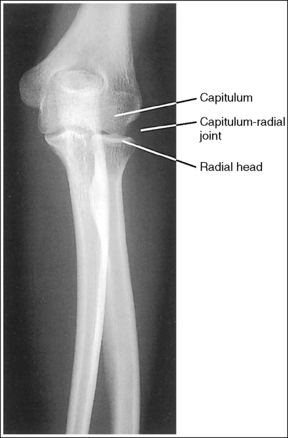

The capitulum and medial trochlea are demonstrated without superimposition, and the radial head is superimposed on only the anterior tip of the coronoid process.

• The axiolateral elbow projection is obtained by placing the patient's elbow in a lateral projection, with the humeral epicondyles aligned perpendicular to the IR and placing a 45-degree proximal (toward the shoulder) angle on the central ray (Figure 4-85). It is this humerus and central ray positioning that accurately separates the capitulum and trochlea of the distal humerus and positions the radial head anteriorly to the coronoid process. The combination of positioning and angulation projects the anatomic structures (radial head and capitulum) situated farther from the IR proximal to those structures (coronoid process and medial trochlea) situated closer to the IR.

The capitulum-radial joint is open, and the proximal radial head and coronoid process are aligned.

• An accurately aligned radial head and coronoid process and an open capitulum-radial head joint is obtained when the elbow is in a lateral projection. A lateral elbow projection is accomplished when the humeral epicondyles are positioned directly on top of each other, placing them perpendicular to the IR (see Figure 4-85).